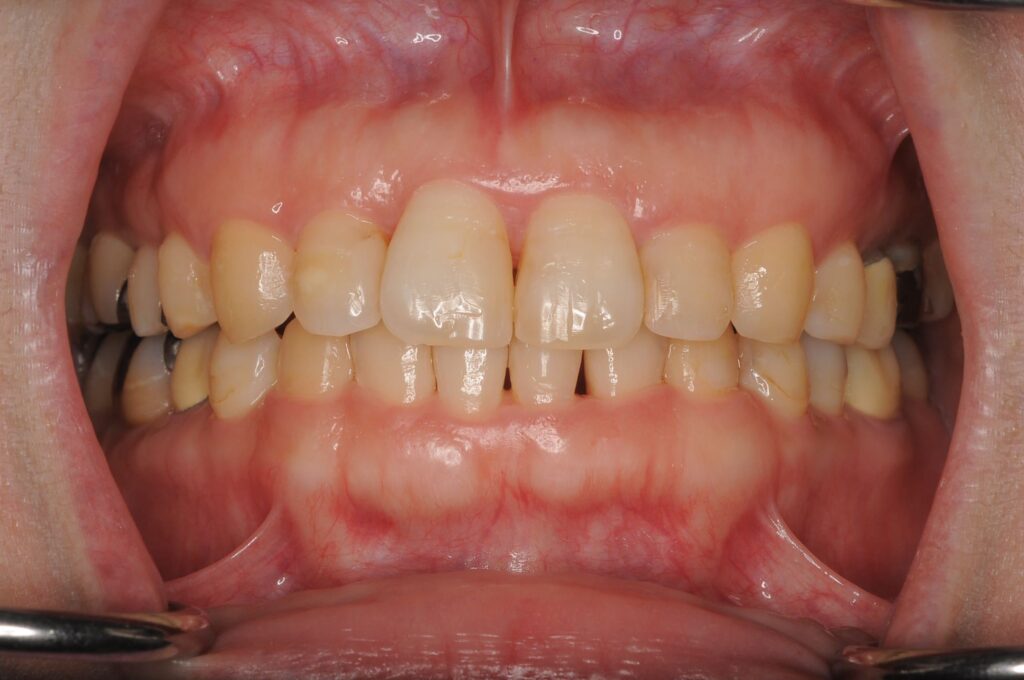

治療を全て終えて、1ヶ月後の写真です。最初から比べたら前歯の状態が整っています。整ったことで歯と歯の間の歯茎に黒い影が目立つようになっています。治療を始める前からある程度予想をして伝えていましたのでトラブルにはなっていません。これ以上悪くならないように経過を診させてもらっています。

治療前の状態がこんな感じでしたから随分良くなったと思います。

5:治療後